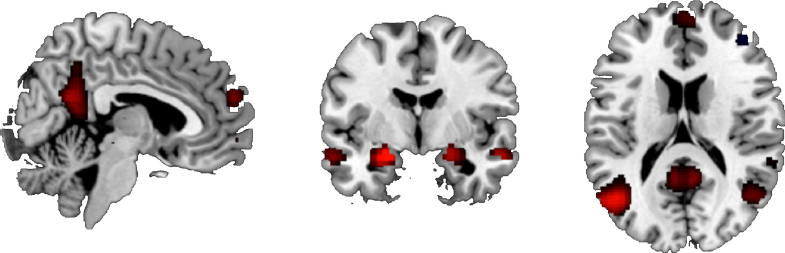

Brain areas involved in emotional processing were activated by the task, in both the Negative minus Neutral contrast and the Positive minus Neutral contrast, see Table 3 and Fig. 2. For the Negative minus Neutral contrast and the Positive minus Neutral contrast, these regions included the amygdala, hippocampus and orbitofrontal cortex.

Fig. 2 Brain activation during the Negative minus Neutral contrast, showing the task effect. P < .05, FWE-corrected.